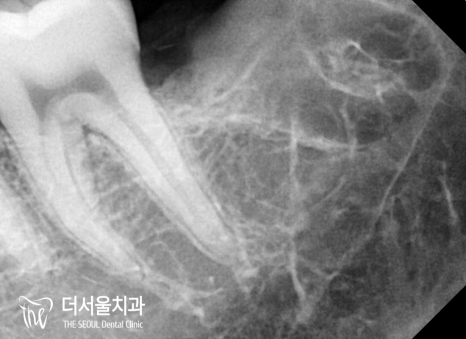

약 10분도 지나지 않고

모든 과정을 마무리할 수 있었습니다.

걱정과는 달리 깨끗하게 뽑힌 것을

확인할 수 있는데요.